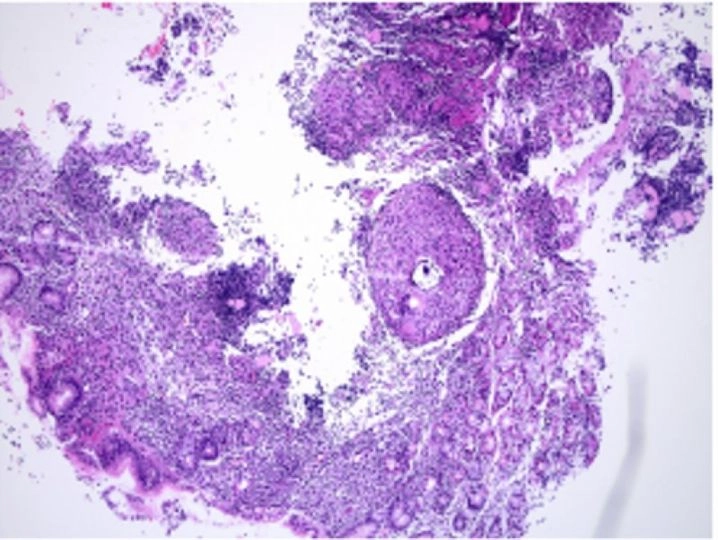

Bộ sưu tập hình ảnh bệnh lao da được tổng hợp từ nhiều nguồn y khoa và thực tế lâm sàng, mang đến cái nhìn trực diện và không che giấu sự thật. Những bức ảnh này không chỉ giúp bác sĩ dễ dàng chẩn đoán mà còn cảnh tỉnh cộng đồng về sự tàn phá âm thầm của căn bệnh quái ác này.